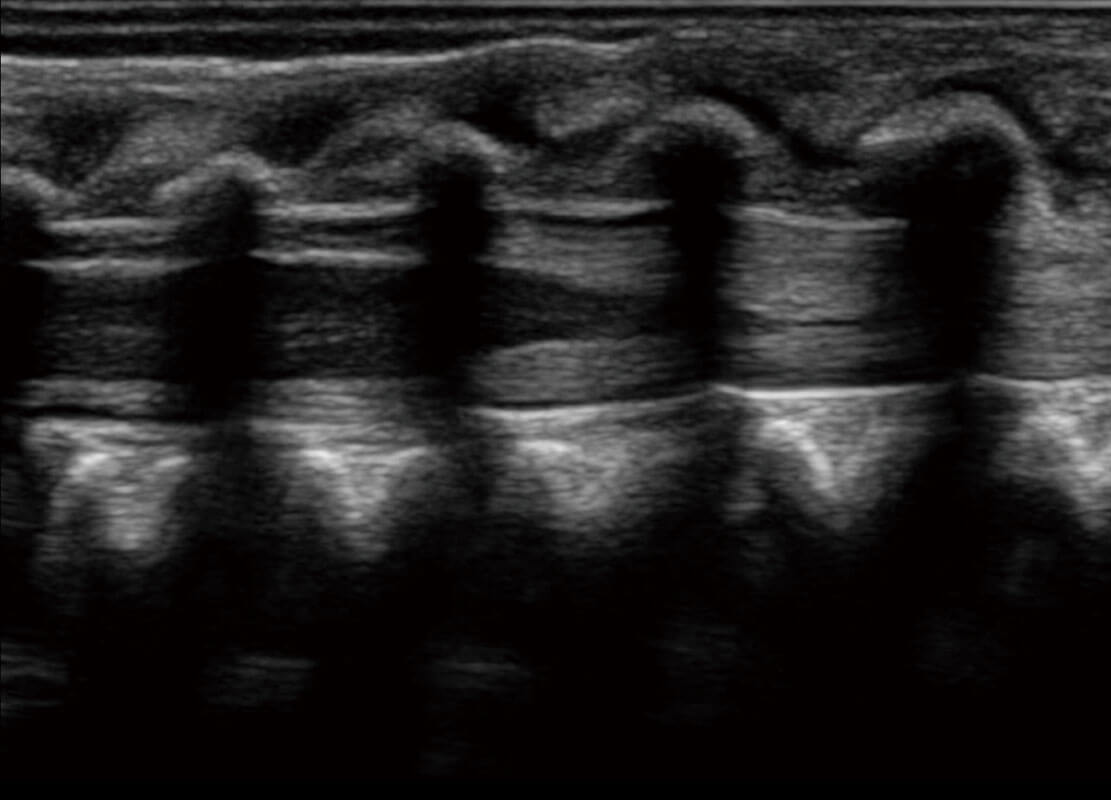

• 四腔切面

• 四腔心血流